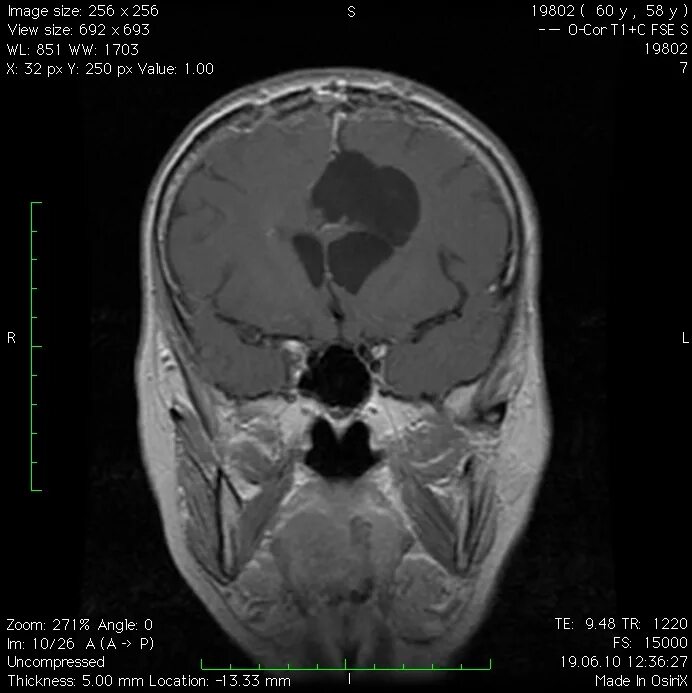

Менингиомы головного мозга мкб